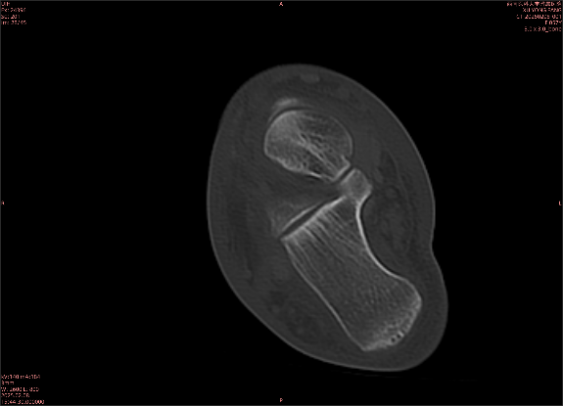

舉例圖像

圖2

專業(yè)解釋看不懂沒關(guān)系,大家看圖1和圖2就可以了,這是同一個(gè)患者跟骨的磁共振和CT圖像,圖1的紅色箭頭指示的黑線就是磁共振圖像顯示的骨折線,一目了然。而對(duì)比圖2的CT圖像上并未顯示異常。